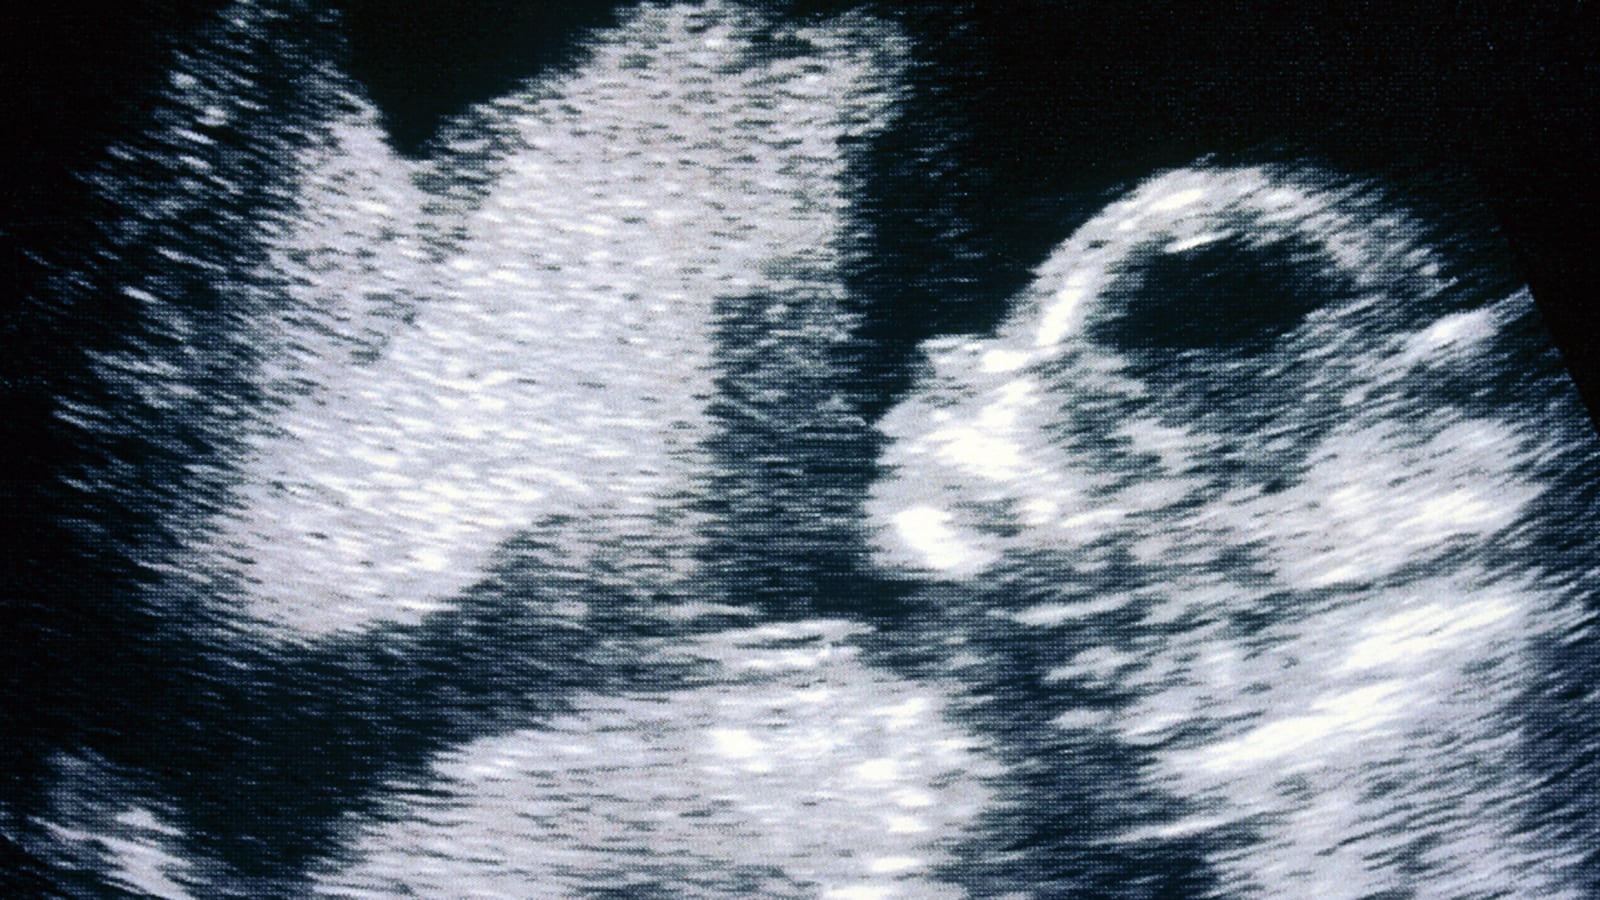

Other parts of the law includes education in public schools prioritizing birth and adoption, signs throughout health-care facilities warning against abortion “coercion,” and an order for the state health department to create and maintain a website touting alternatives to abortion and displaying images of fetuses. Also required is abortion counseling for women aiming to abort pregnancies due to fetal abnormalities, and if the abnormality is certain to be fatal, the counseling incorporates perinatal hospice information before ending the pregnancy. It reaffirms existing barriers to access, like the requirement of a notarized parental consent form for minors and a mandatory ultrasound screening within 24 hours of having an abortion.